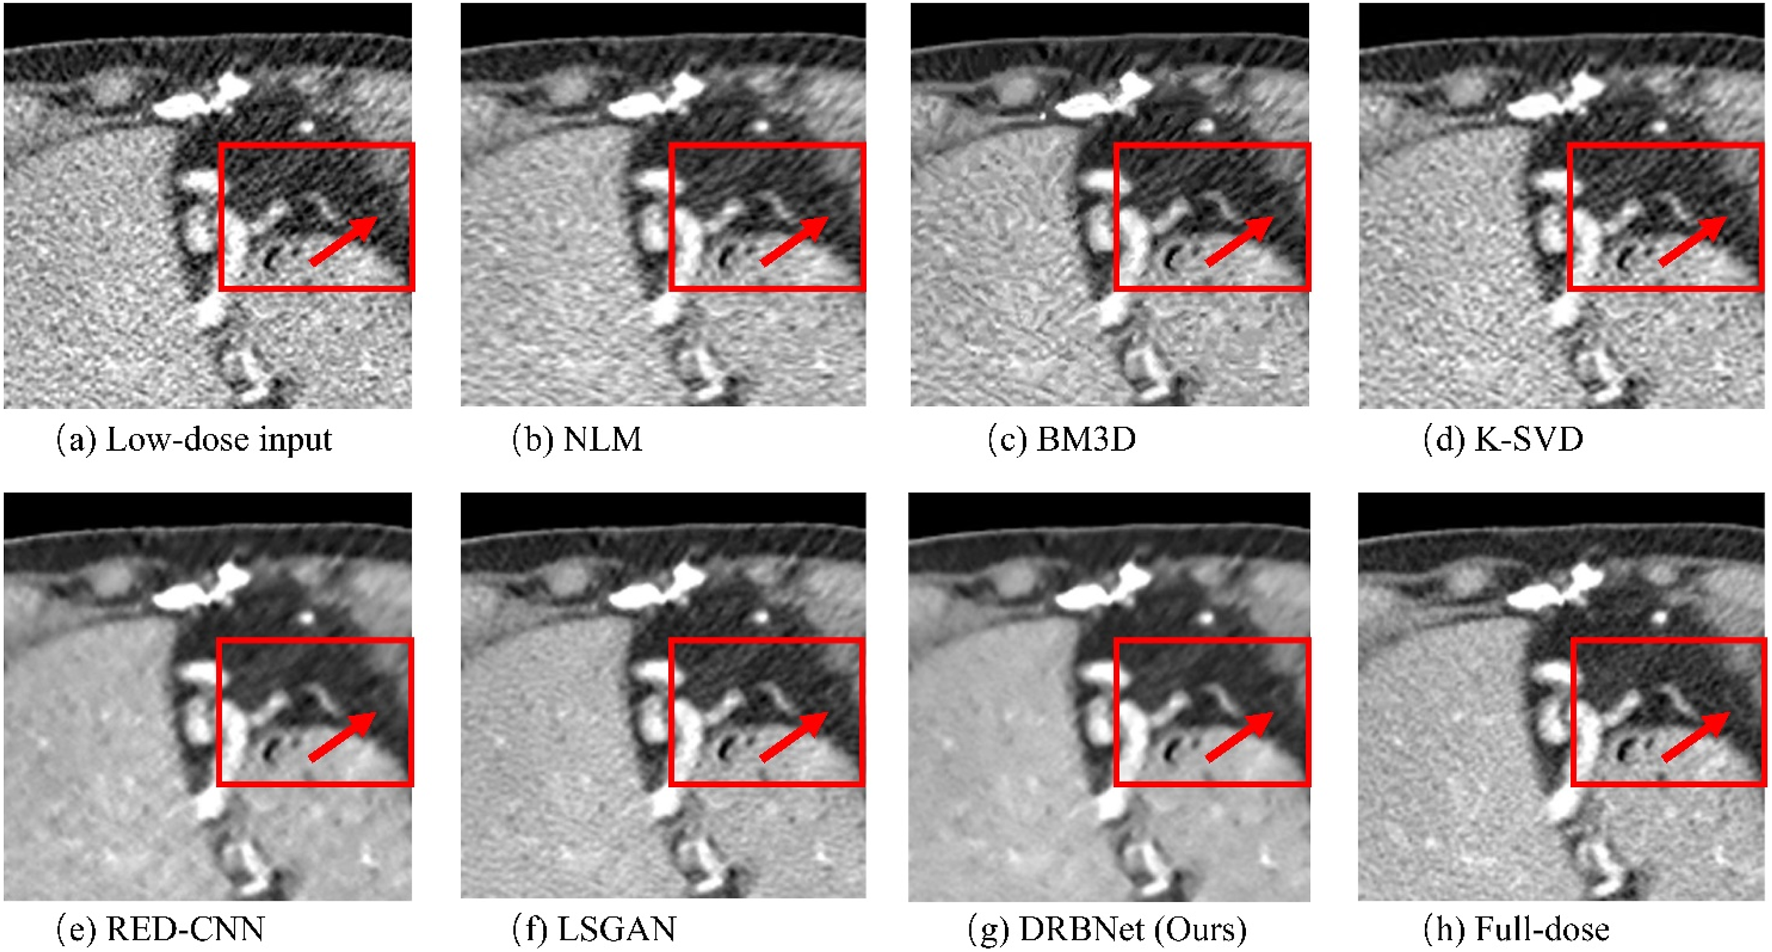

To evaluate the noise reduction performance of our proposed plug-and-play prior for LDCT image denoising, two denoised results of the representative LDCT images are analyzed.

Figures 4–7 show results from proposed DRBNet prior and the compared denoising methods. Figures 4, 5 show the entire CT scans, while Figures 6, 7 focus on the regions of interest (ROIs), marked by red rectangles in Figures 4, 5. The display window for all figures is set to the range of [-160, 240] HU. CT images inherently contain rich textures representing organ and tissue structures. However, as depicted in the figures, the LDCT images are heavily contaminated with noise and artifacts, which can hinder clinicians’ ability to accurately assess lesions, diseases, or tissue morphology. All compared denoising algorithms succeed to some degree in removing noise and artifacts. However, NLM and BM3D provide minimal improvement in noise removal, with noticeable residual noise and artifacts still evident in the enlarged ROI images (see Figure 6b c; Figure 7b,c). The denoising effect of K-SVD is marginally better than that of NLM and BM3D. The results from RED-CNN suffer from over-smoothing, resulting in the loss of fine texture details in the tissue and anatomical structures due to its use of the mean squared error (MSE) loss during training. The denoised CT image from LSGAN reduces noise while maintaining texture information. However, the results obtained using our proposed DRBNet prior, as shown in Figure 4g; Figure 7g, effectively remove noise and suppress artifacts while preserving crucial texture details that are vital for clinical diagnosis.

Figure 6. Zoomed ROI (region of interest) parts of labeled by the rectangle in Figure 3. (a) Low-dose, (b) NLM, (c) BM3D, (d) K-SVD, (e) RED-CNN (f) LSGAN, (g) DRBNet (Ours), (h) Full-dose. The display window ranges: 160 to 240 HU.

Figure 7. Zoomed ROI (region of interest) parts of labeled by the rectangle in Figure 4. (a) Low-dose, (b) NLM, (c) BM3D, (d) K-SVD, (e) RED-CNN (f) LSGAN, (g) DRBNet (Ours), (h) Full-dose. The display window ranges: 160 to 240 HU.

In Figure 6, the zoomed-in ROI, marked in Figure 4 with a red rectangle, contains rich tissue texture information. This ROI section includes intricate tissue details that are nearly obscured by significant noise and artifacts. Notably, the textures indicated by the red arrow in Figure 6a are blurred and unclear in the original LDCT input. The NLM, BM3D, and K-SVD methods struggle to restore these fine textures. RED-CNN causes excessive smoothing, resulting in further blurring, while LSGAN still leaves some residual noise that could affect clinical diagnosis. However, in Figure 6g, the result from our proposed DRBNet prior clearly restores the fine texture and removes the noise. In Figure 7g, the low attenuation lesions, highlighted by the red circle and red arrow, along with the subtle details indicated by the blue arrow, are restored by our approach and closely resemble the full-dose target. Overall, the observations from Figures 4–7 demonstrate that the visual results produced by our DRBNet prior are highly promising.